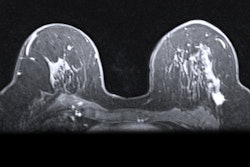

Which breast cancer patients should get preoperative MRI? The answer may not be as clear-cut as some would like to believe. A July 10 study in Radiology: Imaging Cancer found no patient- or tumor-specific factors predicted preoperative breast MRI outcomes.

Multiple prominent cancer and breast health societies recommend preoperative MRI for patients with invasive lobular carcinoma, dense breast tissue, or mammography findings suspicious of additional malignancy. However, few studies have had the patient dataset necessary to validate these recommendations.

For their study, the researchers used data from a large regional cancer center in Washington. Unlike most medical centers, the hospital has conducted preoperative MRI scans for about 90% of breast cancer patients younger than 70 since 2005. The authors used their large, long-term dataset to evaluate whether age, breast density, and other factors were linked to additional malignant tumors in breast cancer patients.